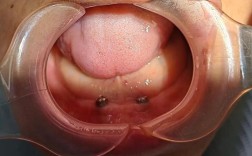

种植体植入与修复

植骨术后需等待4-6个月(自体骨可缩短至3-4个月),待移植骨与宿主骨完全整合(CBCT显示骨密度接近宿主骨),再行二期手术暴露种植区,植入种植体,术后3-6个月,待种植体与骨组织形成骨结合(osseointegration),最终完成牙冠修复,实现功能恢复。